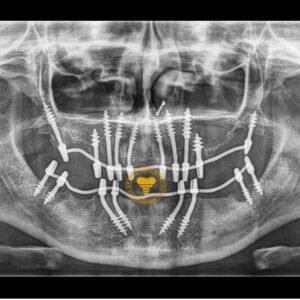

1002 Basal Full Mouth Implants Case Rubeena 2

1002 basal implant full mouth case rub 4